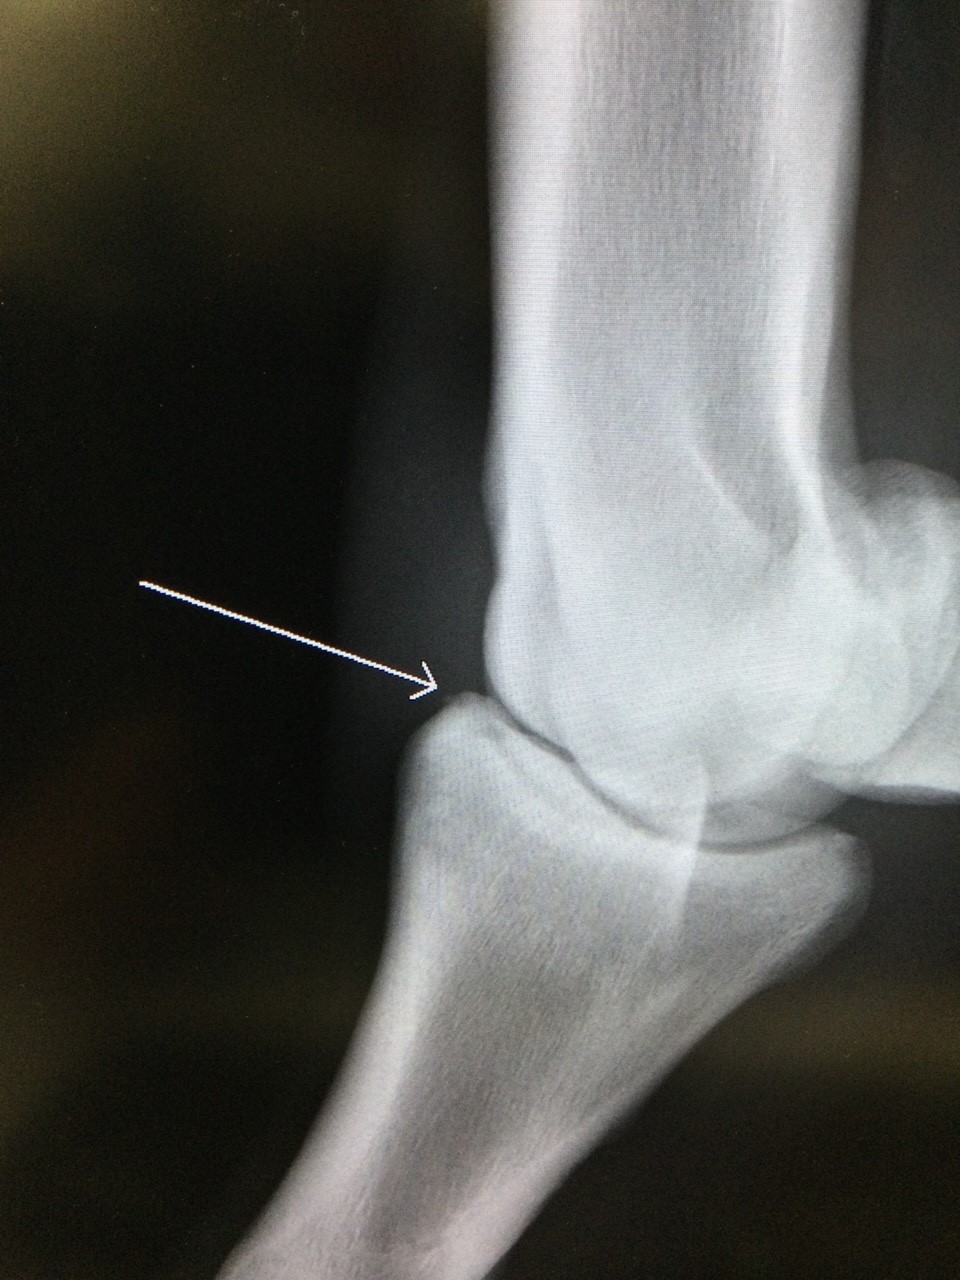

その後は1勝クラスのダート中・長距離でコンスタントに入着を重ね、川崎競馬場で行われた交流競走では1番人気に応え見事2勝目を勝ち取りました。この度、2勝クラスでは上位争いするのが難しいことと、右前第一指骨に小さな剥離(レントゲン写真参照)が見つかったこともありJRAの登録を抹消することといたしましたが、本馬の「先行して、粘り強さを活かす」というレーススタイルは地方競馬にマッチするはずですし、前進気勢にやや欠ける部分があるため地方競馬の騎手との相性も良いと思われます。即通用しても不思議ない実力の持ち主です。なお現状渡しのノークレームノーリターンでお願いいたします。記載事項に関するキャンセルには応じられません。

※2022年6月4日に右前第一指骨剥離骨折を発症。事故見舞金11号(競走中の事故により事故発生の日から3ヵ月以上中央競馬の競走に出走できなくなった場合)を受給しています。

※2021年5月25日(4歳時)に右前腕節部剥離骨折を発症。事故見舞金7号(競走中の事故により事故発生の日から9ヵ月以上中央競馬の競走に出走できなくなった場合)を受給しています。2021年6月に骨片除去及び骨膜クリーニング手術を実施しています。